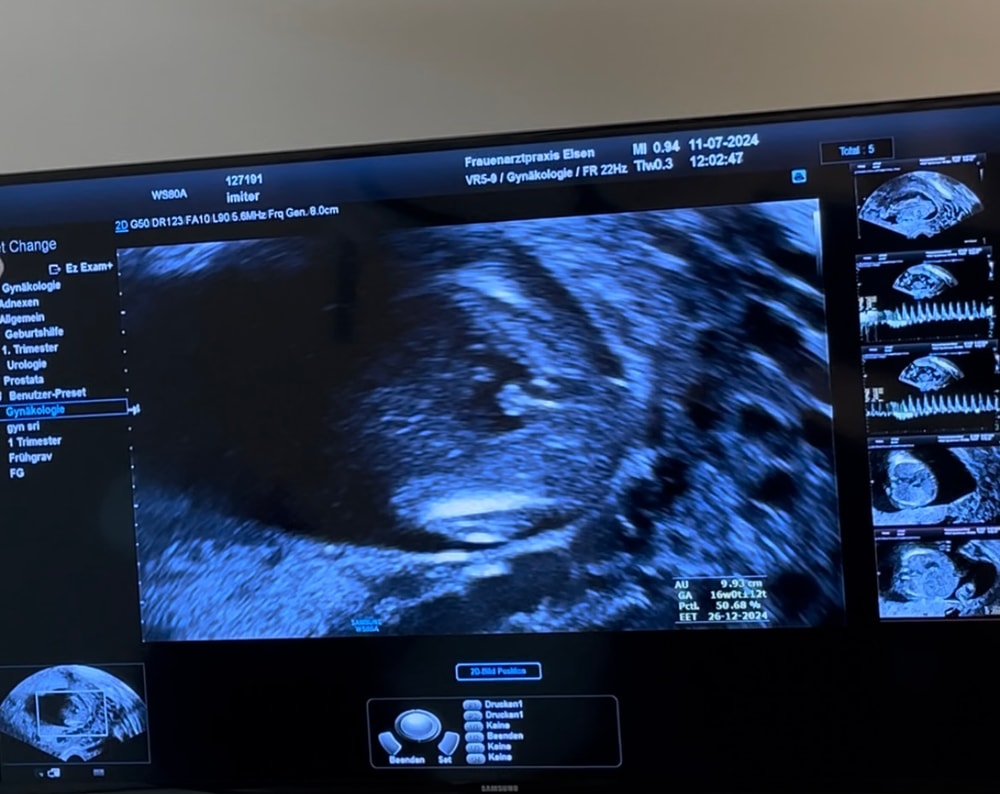

Вот у меня на узи сын))у вас не могу понять,как-будто и да,а как-будто и нет,но больше склоняюсь,что вижу мужские половые органы